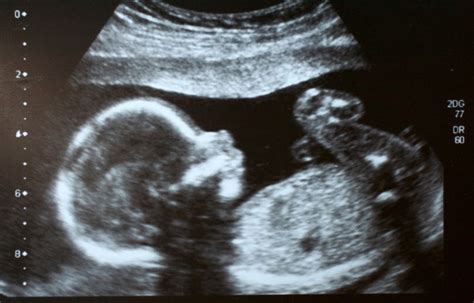

Für die Untersuchung eines ungeborenen Kindes kommen hochauflösende Sonographie, 3D/4D-Darstellung und Farbdoppler zum Einsatz. Das Ersttrimesterscreening zwischen der 11. und 14. Schwangerschaftswoche dient dem Ausschluss von Chromosomenstörungen und kindlichen Fehlbildungen. Eine weitere nicht-invasive Blutuntersuchung der Mutter während der Frühschwangerschaft kann Trisomie 21, 13 und 18 ausschließen.

Die Ultraschallfeindiagnostik im zweiten Trimester, idealerweise zwischen der 20. und 22. Schwangerschaftswoche, ist ein zentraler Bestandteil der fetalen Beurteilung und umfassender als der reguläre Ultraschall. Sie ermöglicht die Abbildung des Kindes in Ergänzung zum konventionellen 2D-Ultraschall.